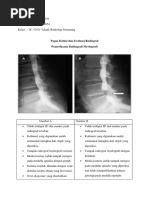

c. Evaluasi

1) Rotasi: simetris sacroilliaca joint

2) Anatomi :

 Ginjal kanan : bentuk, letak, dan axis normal. Kontras

tampak mengisi PCS pada menit ke-5. PCS tak melebar,

kaliks minor bentuk cupping, tak tampak filling defect.

 Ginjal kiri : Ginjal kanan : bentuk, letak, dan axis normal.

Kontras tampak mengisi PCS pada menit ke-5. PCS

melebar, kaliks minor bentuk clubbing, tak tampak filling

defect.

3) Daya tembus: Terlihatnya kedua psoas line

4) Faktor eksposi : Tampak peritoneum fat